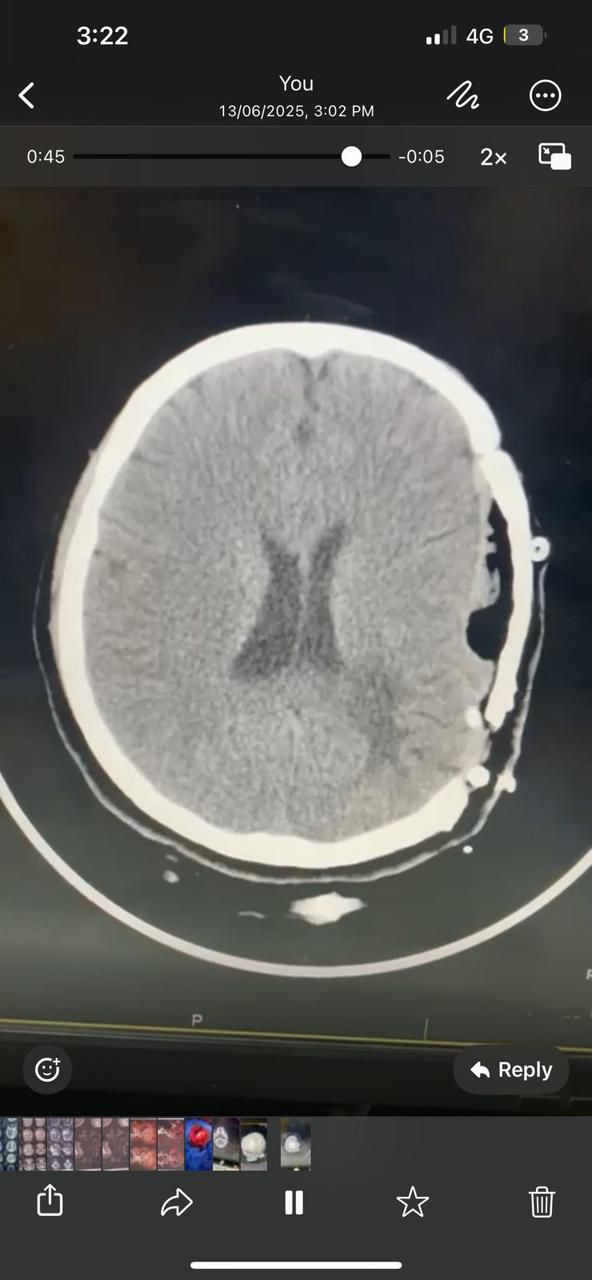

وبعد توقيع الكشف الطبي، تبين أن المريضة كانت قد تعرضت في وقت سابق لنزيف تلقائي حاد في أنسجة المخ، وخضعت لجراحات سابقة شملت رفع جزء من عظام الجمجمة وزرعها مؤقتًا بالتجويف البطني لتخفيف الضغط الدماغي.

وقد أجريت للمريضة الفحوصات الطبية اللازمة، شملت: أشعة مقطعية على المخ ورنين مغناطيسي على شرايين وأوردة الدماغ وتكوين ثلاثي الأبعاد لشبكة الشرايين الدماغية.

كما أظهرت الفحوصات احتمالية تشوه شرياني وريدي أو حوصلة دموية كهفية متكلسة، إلا أن الشرايين الرئيسية بالمخ ظهرت سليمة ومع الرعاية الطبية والمتابعة الدقيقة، بدأت الحالة في التحسن التدريجي باستخدام مضادات الالتهاب والتورم.